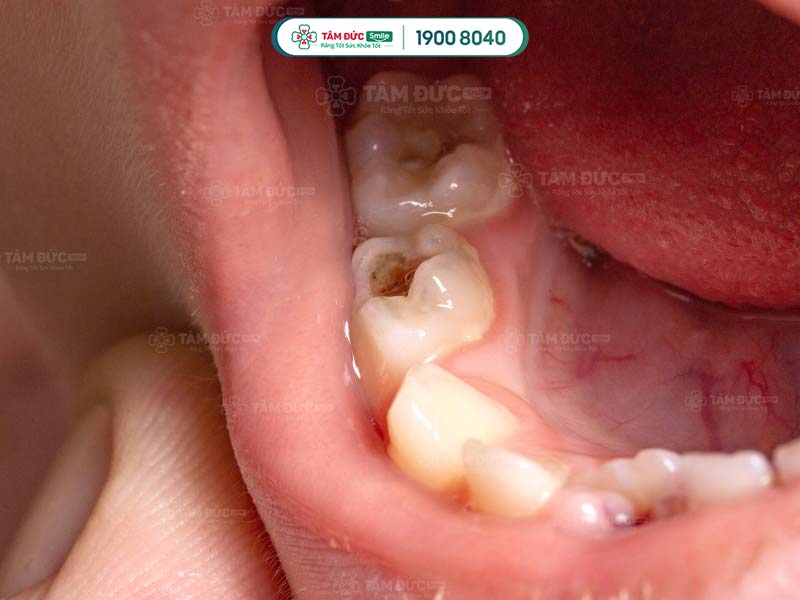

Sâu răng làm cho thân răng và mặt nhai của răng xuất hiện những lỗ nhỏ màu đen. Càng để lâu, vi khuẩn phá hủy men răng càng nặng và trở thành nơi giắt thức ăn vào.

Sâu răng gây đau nhức dai dẳng